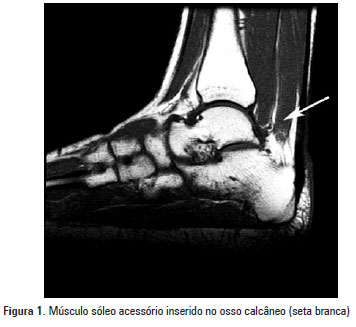

Estudo da presença do músculo sóleo acessório em humanos

DOI: 10.1590/S1679-45082012000100016

OBJETIVO: Verificar a prevalência do músculo sóleo acessório em humanos e em relação ao gênero. MÉTODOS: Foram observadas 154 imagens de ressonância magnética do tornozelo em cortes sagitais, coronais e axiais ponderadas em T1. RESULTADOS: Observamos a incidência de 11,6% do músculo sóleo acessório em humanos – 7,8% em indivíduos do gênero masculino e 15,6% em indivíduos do gênero feminino. CONCLUSÃO: O músculo sóleo acessório teve incidência de 11,6% nas amostras estudadas e sua presença foi maior em indivíduos do […]

Palavras-chave: Diagnóstico por imagem; Espectroscopia de ressonância magnética; Músculo esquelético; Tornozelo